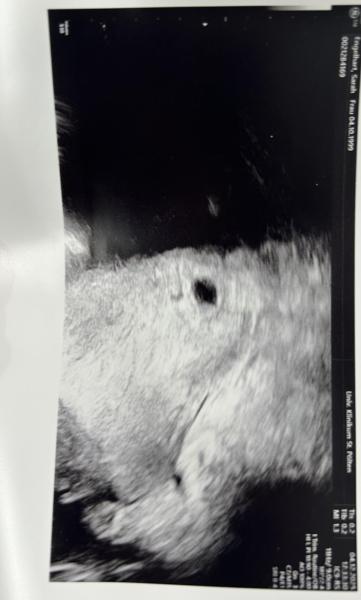

Hallo meine Lieben, mich hätte mal eine Frage (ist meine erste SS und ich bin sehr unsicher/aufgeregt). Ich war heute beim Ultraschall und da konnte man nur eine Fruchthöhle (10mm) sehen, der OA meinte, dass ich mich in der SSW 5+5 befinde. Mein HCG Wert im Blut wurde gestern (03.12)  bereits gemessen, dieser betrug 13132, am 25.11 fand die erste Messung statt da war er erst bei 245. Der Arzt war etwas verwundert von dem hohen HCG Wert. Hat von euch da vielleicht jemand Erfahrungswerte?

Bild zu SSW 5 + 5 - hoher HCG Wert - nur Fruchthöhle zu sehen - Kinderwunsch - was tun, um schwanger zu werden?